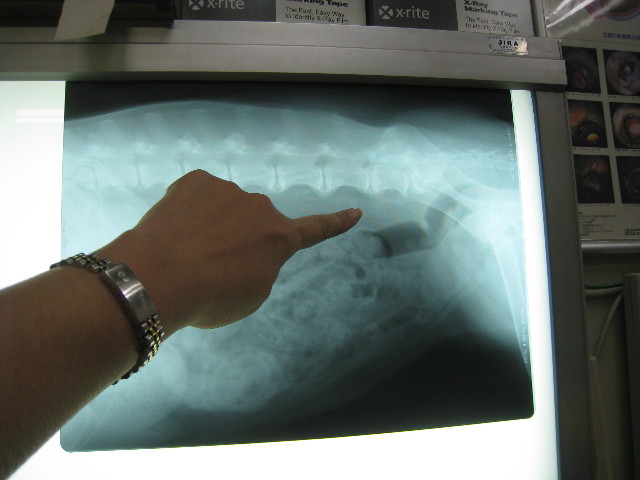

リンパの様子をみるためにとりあえずレントゲンを2枚とった。

指で指したあたりが、腰回りに通じるリンパのある位置なんだって。

今のところリンパの腫れや転移を疑わせるようなものはないみたい。

(きちんと診るにはCTが良い)